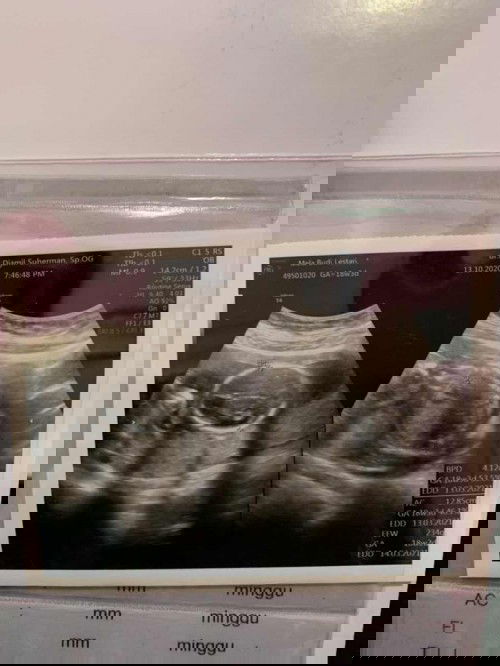

Usg 17 weeks

Assalamualaikum bunda Ini aku lagi posisi sujud + lagi sembunyi 😂 Posisiku membelakangi mama Dan Cuman aku kasih lihat punggungku biar mama penasaran 😍

Usg 17 minggu

Assalamualaikum bundaaaa Mau sharing dong kira kira diusia brapa minggu ya jenis kelamin dedek bayi bisa terdeteksiii Gemes banget bunda kepengen cepet tau penasaran gtu hehe InshaAllah tgl 6 mau usg usia janin memasuki 17 minggu lebih 5 hari